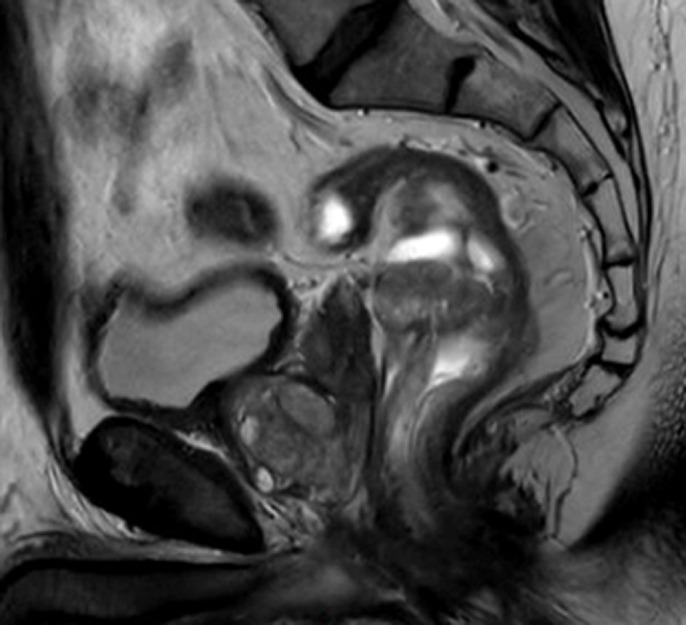

Epithelial tumors with neuroendocrine and nonendocrine components constitute the rare yet aggressive entity of neoplasms of the gastro-entero-pancreatic tract. These tumors were first named "mixed adeno-neuroendocrine carcinomas" (MANECs) by the World Health Organization in 2010 and in 2017 renamed "mixed neuroendocrine non-neuroendocrine neoplasms" (MiNENs). Combined adenocarcinoma and neuroendocrine carcinoma neoplasms are a rare occurrence within the gastrointestinal tract. In this report, we describe two separate cases of mixed rectal adeno-neuroendocrine carcinomas and their treatment. We describe two cases at one institution of mixed neuroendocrine non-neuroendocrine rectal neoplasms. Given the rarity of diagnosis and inconsistencies in both nomenclature and treatment recommendations in the literature, mixed adeno-neuroendocrine carcinoma epidemiology and prognosis are not yet fully understood. Future prospective trials with a focus in management of MiNENs will offer valuable insight into these rare mixed carcinomas.